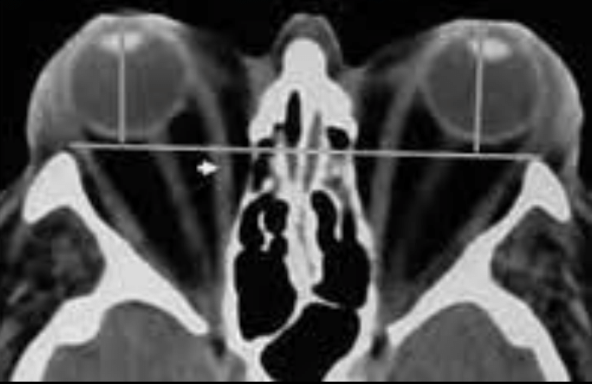

¿Qué signos observamos en TC y RM de exoftalmos?

Protrusión ocular anormal

Disociación del índice globo ocular-línea intercantal

- Masas ocupativas retrooculares

¿Qué observas?

Aumento de grasa intraorbital y protrusión ocular